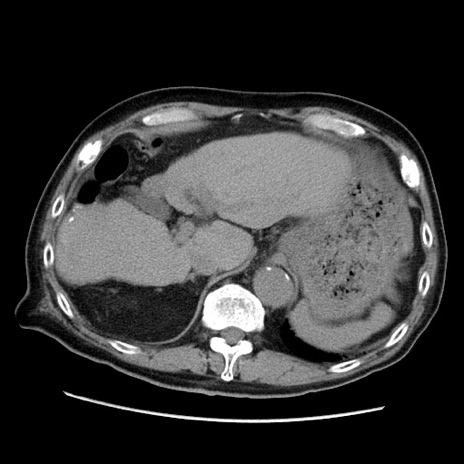

症例21(横断像)

【症例】70歳代男性

【主訴】腹痛

【現病歴】肝硬変・肝細胞癌にてかかりつけの方。約9時間前に食後より腹痛出現。症状が徐々に増悪し、嘔吐出現したため来院。

【既往歴】肝硬変、肝細胞癌(RFA、TACE後)

【身体所見】意識清明、表情苦悶様、BT 36℃、BP 129/78mmHg、P 88bpm、SpO2 97%(RA)、右上腹部から心窩部にかけて圧痛あり、反跳痛なし、筋性防御あり。

【データ】WBC 5800、CRP 0.16